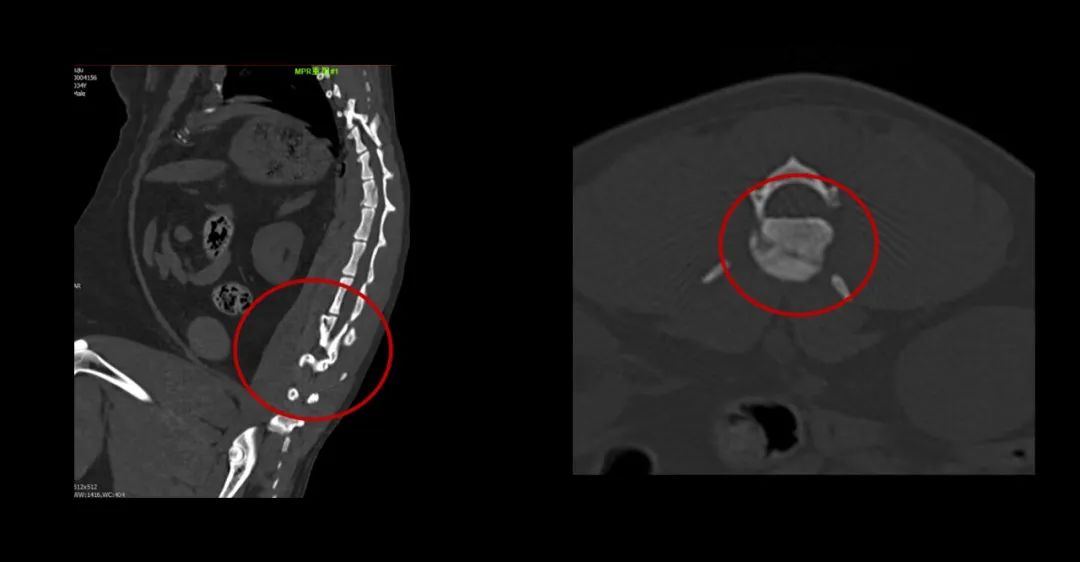

▲寵物也喜歡吃燒烤,可惜竹簽卡在食道里了。

▲俗話說“貓有九條命”,可不能當(dāng)真哦。你看看這兩個(gè)小家伙從樓上高空落地,一只左側(cè)股骨遠(yuǎn)端骨折,另一只第1腰椎椎體骨折。